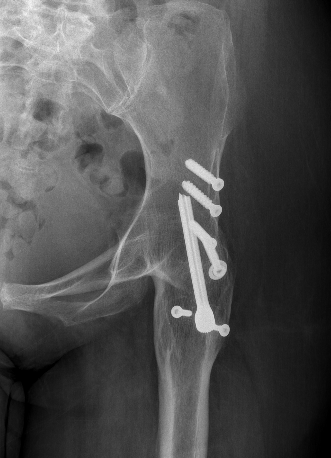

Extra-articular Intra-articular Combined intra-articular + anterior plate

Hip Fusion Cobra Plate Hip Fusion AP Hip Fusion 1Hip fusion 2

Fixation

- 150° DHS / 6.5 mm cannulated screws

- through joint into thick supra-acetabular area of ilium

- supplement with additional screws as necessary

Anterior plate onto lateral aspect of iliac crest